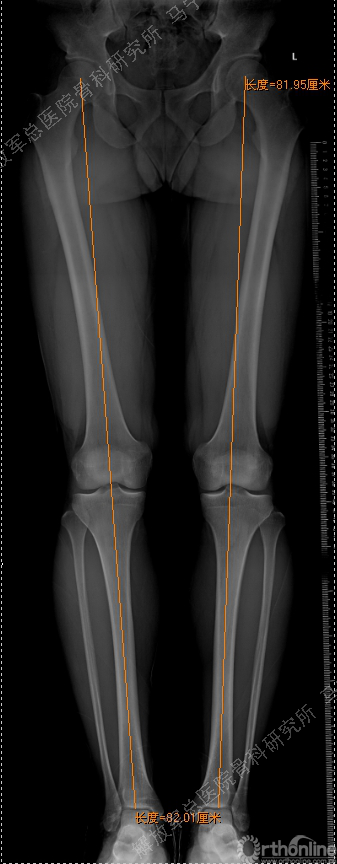

虽然是软骨损伤,但也需要X线评估关节结构,测量双下肢力线,髌骨轨迹,Q角等,排除结构因素引起的软骨损伤,若术前存在发育不良,脱位,半月板损伤,交叉韧带损伤,必须先进行矫形,最后再进行软骨修补,才能达到最佳效果和持久性。